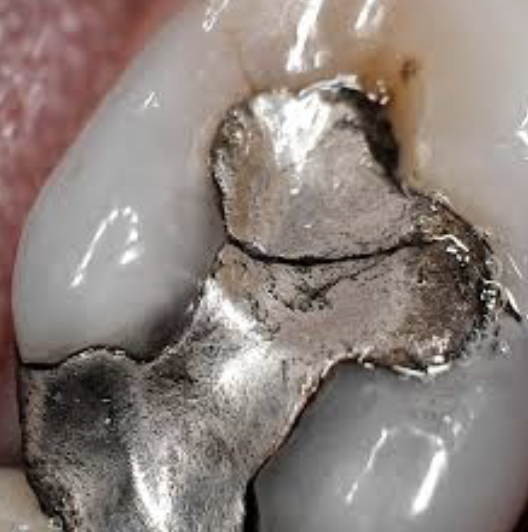

Fig 6. Intra-oral photography. Lower lingual anterior gingiva (Fig 5). Old restoration (Fig 6).

Figure 6

Intra-oral photography. Many dental conditions involve the margins between the natural tooth and the old restoration, which can be difficult to adequately capture with either traditional radi- ography or extra-oral photography. Every operatory should therefore be equipped with a high-quality intra-oral camera; sharing such photographs with the patient during the consultation is quite helpful in explaining the need for longer-term restorations. A well-trained dental hygienist or assistant can quickly  and seamlessly integrate several intraoral photographs during the new patient interview (Figure 5 and Figure 6), discussed below.